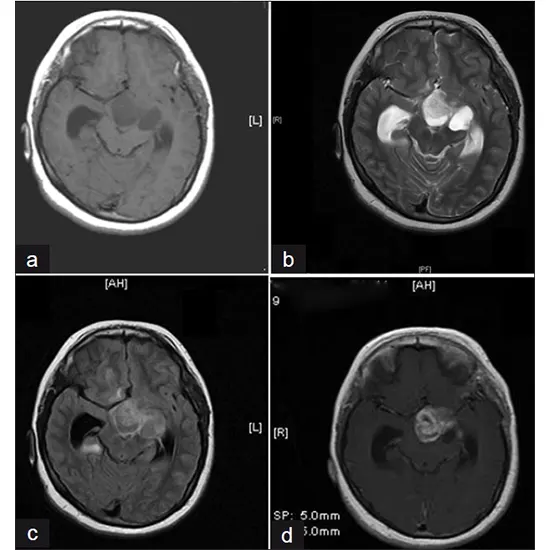

Diagnosis of hypothalamic gliomas typically involves imaging studies such as magnetic resonance imaging (MRI) or computed tomography (CT) scans to visualize the tumor and its relationship to the surrounding structures, including the visual pathway and hypothalamus. A biopsy may be performed to confirm the diagnosis and determine the type and grade of the tumor.